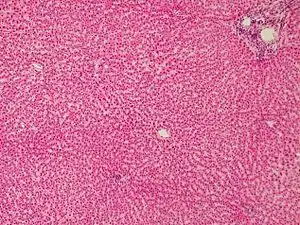

Гистология

Это крупные клетки полигональной или шестиугольной формы. Имеют одно или несколько ядер, при этом ядра могут быть полиплоидными. Многоядерные и полиплоидные гепатоциты отражают приспособительные изменения печени, поскольку эти клетки способны выполнять гораздо более интенсивно свои функции, чем обычные гепатоциты. Каждый гепатоцит имеет две стороны: васкулярную и билиарную. Васкулярная сторона обращена в сторону синусоидного капилляра. Она покрыта микроворсинками, которые проникают через поры в эндотелиоците в просвет капилляра и прямо контактируют с кровью. От стенки синусоидного капилляра васкулярная сторона гепатоцита отделяется перисинусоидальным пространством Диссе. В этом щелевидном пространстве находятся микроворсинки гепатоцитов, отростки печеночных макрофагов (клеток Купфера), клетки Ито и иногда — Pit-клетки. В пространстве встречаются также единичные аргирофильные волокна, количество которых увеличивается на периферии дольки. Таким образом, в печени отсутствует типичный паренхиматозный барьер (имеется так называемый "прозрачный" барьер), что позволяет веществам, синтезируемым в печени, попадать прямо в кровь. С другой стороны, из крови в печень легко поступают питательные вещества и подлежащие обезвреживанию яды. Васкулярной стороной гепатоцит захватывает также из крови секреторные антитела, которые затем поступают в желчь и оказывают свой защитный эффект. Билиарная сторона гепатоцита обращена в сторону желчного капилляра. Цитолемма контактирующих гепатоцитов здесь образует инвагинации и микроворсинки. Вблизи образовавшегося таким образом желчного капилляра цитолеммы контактирующих гепатоцитов соединяются при помощи опоясывающих десмосом, плотных и щелевидных контактов. Билиарной стороной гепатоцитов вырабатывается желчь, которая поступает в желчный капилляр и далее в отводящие протоки. Васкулярная сторона выделяет в кровь белки, глюкозу, витамины, липидные комплексы. В норме желчь никогда не поступает в кровь, потому что желчный капилляр отделен от синусоидного капилляра телом гепатоцита.